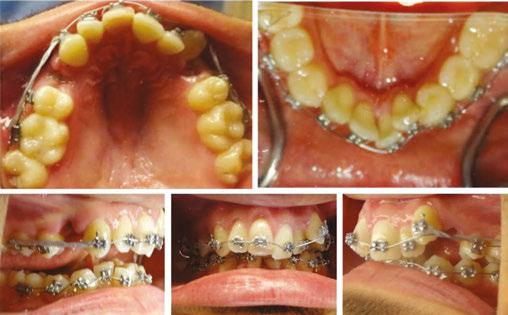

Patient examination

A 23-year-old male presented to our clinic with a chief complaint of severe crowding and “crooked” teeth in both arches. An extraoral evaluation revealed the patient was mesocephalic, with a slightly convex profile, symmetrical face and jaw, and competent lips (Figure 1).

The intraoral examination revealed moderate maxillary crowding and severe mandibular anterior crowding, Class I molar relationship, occlusal cant (Figure 2D), and an ectopic upper left canine (Figure 2E). Both arches displayed discrepancies in arch length, particularly the mandibular arch, and each showed tapered arch forms (Figures 2A and 2B). A Bolton discrepancy was also noted. A Class IV composite restoration was also present on tooth No. 8.

Jeffrey Miller, DDS, is an orthodontic specialist in private practice, Orthodontic Associates, in Maryland. He speaks both nationally and internationally on CBCT topics related to orthodontics. Please feel free to email Dr. Miller at dr.miller@ orthodonticassoc.com with questions Claire Miclat, DDS, is a matriculating orthodontic resident at Indiana University. Figure 1: Initial pretreatment extraoral photos taken on December 17, 2020 Figure 2: Initial pretreatment intraoral photos taken on December 17, 2020 A. C. D. E. B.

It was clear that extractions were going to be necessary to relieve crowding for this patient. It was unclear which mandibular teeth would be best suited for extraction, considering that tooth Nos. 24, 26, and 27 were ectopic and considerably displaced out from the center of the alveolar housing or trough (Figure 2B). Additionally, tooth No. 24 was already showing signs of gingival recession (Figure 2D), further suggesting its position within the alveolar housing was compromised.